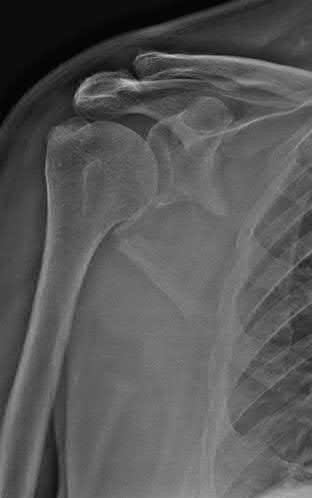

Question 2:

A 28-year-old male sustains a severe hyper-dorsiflexion injury to his ankle in a motor vehicle accident, resulting in a Hawkins Type III talar neck fracture. Which of the following arteries provides the predominant blood supply to the body of the talus, placing it at significant risk for avascular necrosis in this injury?

Correct Answer: Artery of the tarsal canal

Explanation:

The artery of the tarsal canal, which is a branch of the posterior tibial artery, provides the dominant blood supply to the talar body. In a Hawkins Type III fracture (talar neck fracture with subtalar and tibiotalar dislocation), the blood supply from the artery of the tarsal canal, the artery of the sinus tarsi, and capsular vessels are disrupted, leading to an avascular necrosis (AVN) rate approaching 100%.